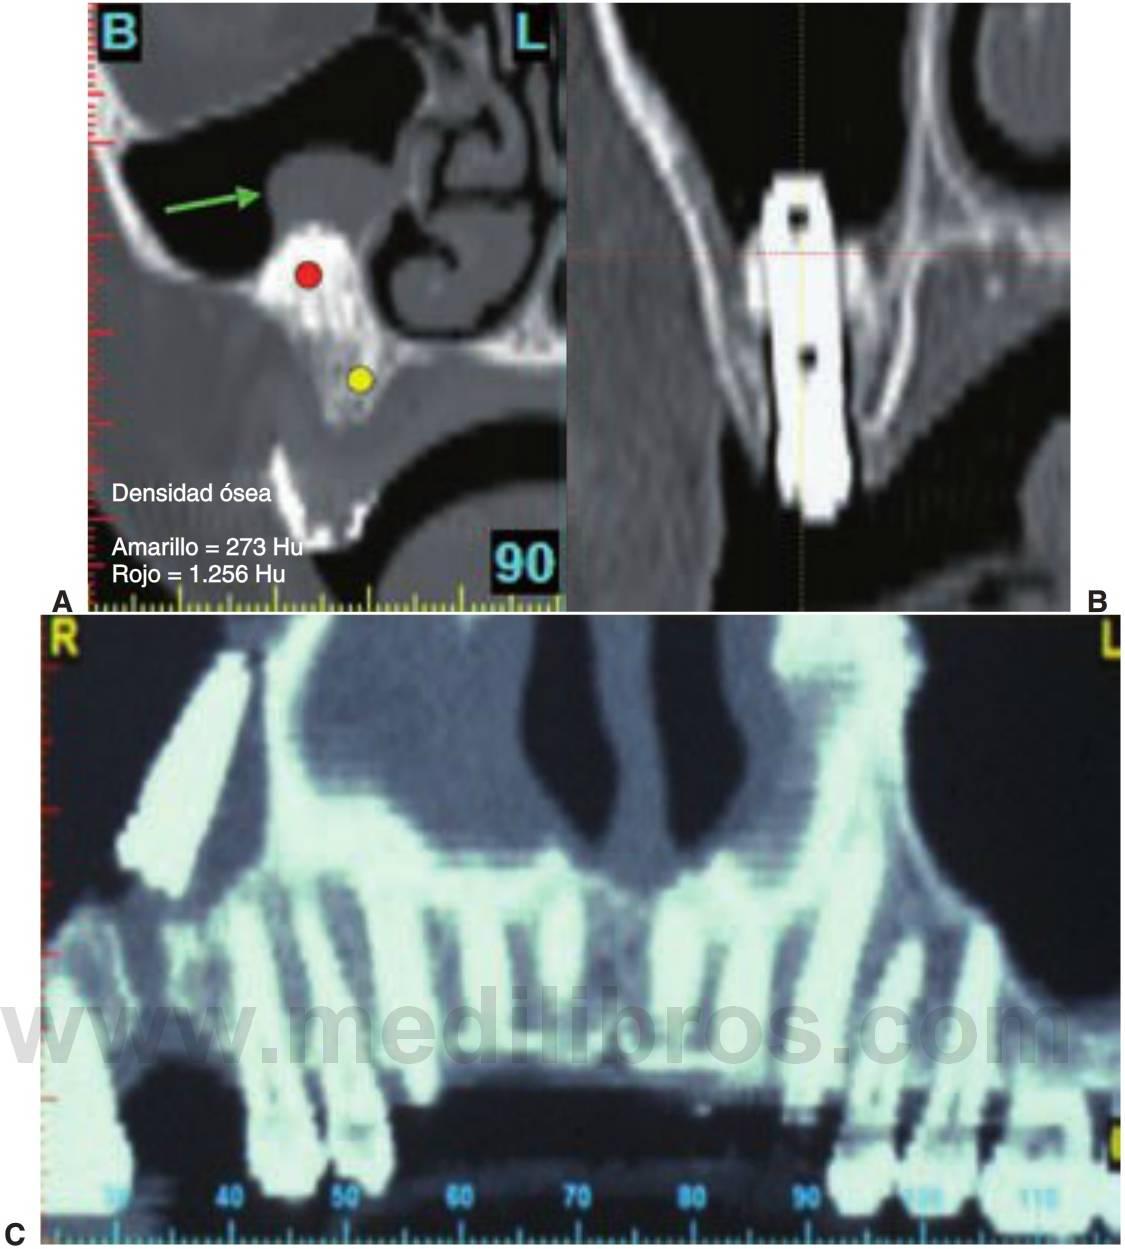

La TC produce imágenes axiales de la anatomía del paciente. Las imágenes axiales se producen perpendiculares al eje largo del cuerpo. La TC es una técnica prospectiva de imagen digital. La fuente de rayos X es sujetada rígidamente a un detector geométrico de haces en abanico desplegado, que rota 360 grados alrededor del paciente y recoge los datos. El detector de imagen es gaseoso o de estado sólido, produciendo señales electrónicas que sirven como datos para introducir en unordenador conectado. El ordenador procesa los datos empleando técnicas algorítmicas de retroproyección de Fourier, desarrolladas por primera vez por Hounsfield para producir las imágenes de TC. Las imágenes de TC son en sí mismas imágenes digitales en tres dimensiones, típicamente de 512 x 512 píxeles con un espesor definido por la separación de los cortes de la técnica de imagen. El elemento individual de la imagen de TC es el vóxel, que tiene un valor, referido en unidades de Hounsfield, que describe la densidad de la imagen de TC en ese punto. Cada vóxel contiene 12 bits de datos y va desde los -1.000 (aire) hasta los +3.000 (esmalte/materiales dentales) de unidades Hounsfield. Los escáneres de TC tienen un valor estandarizado de Hounsfield de0 para el agua. La escala de densidad de los TC es cuantitativa y significativa en cuanto a la identificación y diferenciación de las estructuras y los tejidos.

El poder y la utilidad del TC en la imagen y el diagnóstico maxilofacial se volvieron evidentes tan pronto como se introdujeron los TC de alta resolución a principios de la década de 1980. La TC se empleaba para producir imágenes de la articulación temporomandibular, la evaluación de lesiones dentales/óseas, la evaluación de las deformidades maxilofaciales, y la evaluación preoperatoria y postoperatoria de la región maxilofacial. La TC proporciona unos medios únicos de análisis postimágenes de la cirugía propuesta o de los lechos implantológicos reformateando el dato de la imagen para crear imágenes tomográficas tangenciales y de cortes de sección del sitio del implante. Con los escáneres TC de actual generación, las imágenes reformateadas se caracterizan por un espesor de sección de 1 pixel (0,25 mm) y una resolución de plano in terno de 1 pixel por la distancia de barrido (0,5 a 1,5 mm), produciendo una resolución geométrica similar al de una imagen plana. La densidad de las estructuras dentro de la imagen es absoluta y cuantitativa y puede emplearse para diferenciar los tejidos en la región y caracterizar la calidad ósea (fig. 3-10; cuadros 3-8 y 3-9).

Las ventajas de las imágenes de TC son numerosas, con la magnificación siendo casi del 0 % sin superposición alguna de las imágenes y con una distorsión mínima. La densidad del hueso puede valorarse también exponiendo todas las imágenes como unidades Hounsfield. Al comparar la TC con otros tipos de modalidades radiológicas, la TC ha demostrado ser superior en la identificación de estructuras vitales y en el cálculo de las medidas de distancias76 (v. cuadro 3-10).

Una característica importante de la TCI es que el odontólogo y el radiólogo pueden llevar a cabo cirugía electrónica (CE) seleccionando y colocando cilindros de tamaño arbitrario que simulan la forma de la raíz de los implantes en las imágenes. Con una plantilla diagnóstica adecuadamente diseñada la CE puede llevarse a cabo para desarrollar electrónicamente la planificación del tratamiento del paciente en tres dimensiones. Los implantes electrónicos pueden colocarse en posiciones y orientaciones arbitrarias unos respecto de los otros, de los alveolos, de las estructuras críticas, y de la oclusión prospectiva y de la estética. La cirugía electrónica y la TCI permiten el desarrollo de una planificación de tratamiento en tres dimensiones que se integra en la anatomía del paciente y puede ser visualizado antes de la cirugía por miembros del equipo implantológico y el paciente para su aprobación o modificación. La TCI permite la determinación de la calidad ósea adyacente a los lechos implantológicos prospectivos (figs. 3-14 a 3-16). Una vez determinados con exactitud el número y tamaño de los implantes, junto con la densidad ósea en los sitios implantológicos propuestos, el odontólogo puede determinar con exactitud las características de los implantes antes de la cirugía.